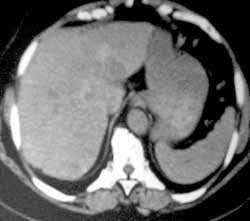

Рис. 1. Рак печени. (Слева) При КТ органов брюшной полости до химиоэмболизации  во II сегменте нечётко определяется патологический очаг размером до 2,0 см. (Справа) После введения масляных химиоэмболов денситометрическая плотность образования резко увеличилось.